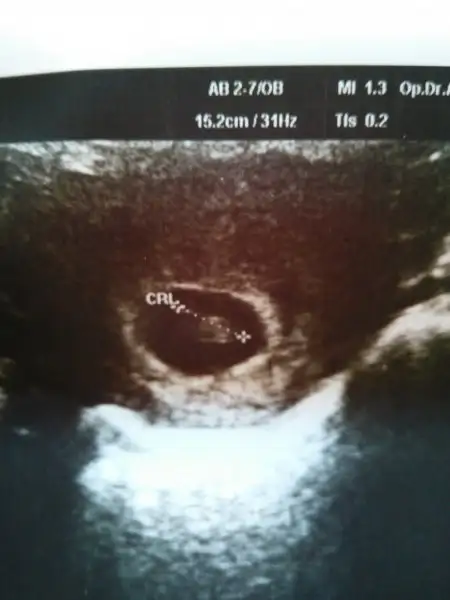

canım bu ultrason karından bahsettiğin hare sağ altta. bu durumda karından olduğu için sol sayılıyor değil mi? yani bu teoriye göre kız. başarabilirsem ultrason fotosunu atacağım canımKesenin sağda veya solda olması önemli değil canım kesenin etrafını saran hale gibi beyaz renkli alan yani plasentanın konumuna göre cinsiyet tahmini yapmışlar.

Evet canım kız oluyor ama hep 6-8 hafta arası denmiş. O tarihten sonra konum değişir mi bilmiyorum . ama bunlar eğlence. Doğrusunu Rabbim bilircanım bu ultrason karından bahsettiğin hare sağ altta. bu durumda karından olduğu için sol sayılıyor değil mi? yani bu teoriye göre kız. başarabilirsem ultrason fotosunu atacağım canım

hare sanki sol altta şayet ultrason karındansa erkek oluyor değil mi?Yüklüyorum canım sen bi incele bakalım. Benim bir kızım var 1 yaşında ikinci biraz erken oldu ama şimdi alıştım. Tabi ki bu cinsiyet tahminlerine inanmıyorum. Tutsada denk geldiğinden.

Ultrason karından bu benim ilk randevumdu. Bi daha da gitmedim. 1 ay sonra tekrar gidip karşılaştırmak istiyorumhare sanki sol altta şayet ultrason karındansa erkek oluyor değil mi?

Buna gore erkek olmasi gerek :)Görüntülerin ikisi de karından bakılan foto sizce benim bebeğim cinsiyeti nedir